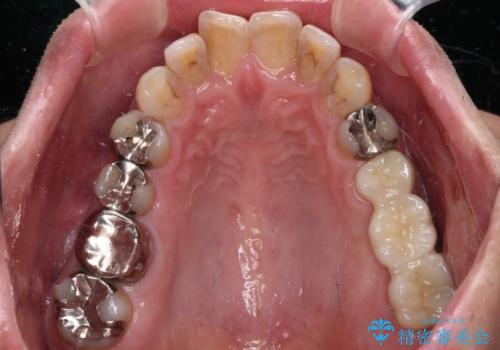

欠損と痛み 奥歯のむし歯治療

- 根っこの一部だけになった歯と咬むと痛みのある歯を気にして来院された患者様です。

上顎の歯根のみとなった歯は抜歯が必要であったので、抜歯を行い、インプラントあるいはブリッジのよる補綴治療を提案しました。

前後の歯は銀歯が装着されていたため、ブリッジによる補綴治療として、前後の歯もセラミックに置き換えることとしました。

下顎の根管治療がされた大臼歯は咬合時に痛みが認められたため、再度根管治療を行った後に補綴治療することとしました。